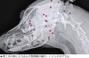

【レントゲン写真】捨て犬の体内に大量の弾片

VIP動物医療センターが25日に明らかにしたところによると、先日保護された捨て犬の体に、散弾銃の破片が70個以上刺さっていることが分かった。

この犬は保護された当時、外見上は銃弾の痕が確認できなかったという。海外の里親に譲渡するために健康診断を受けたところ、レントゲン写真で散弾銃の破片が見つかり、これが原因で海外への譲渡も不可能になった。

VIP動物医療センターのアン・スンヨプ院長は「銃弾が頭部から肩、胸、尻、脚まで多数突き刺さっていた」「生きているのが奇跡」と話した。

• ▲体に散弾銃の破片が多数刺さっているのが見つかった捨て犬。/インスタグラム